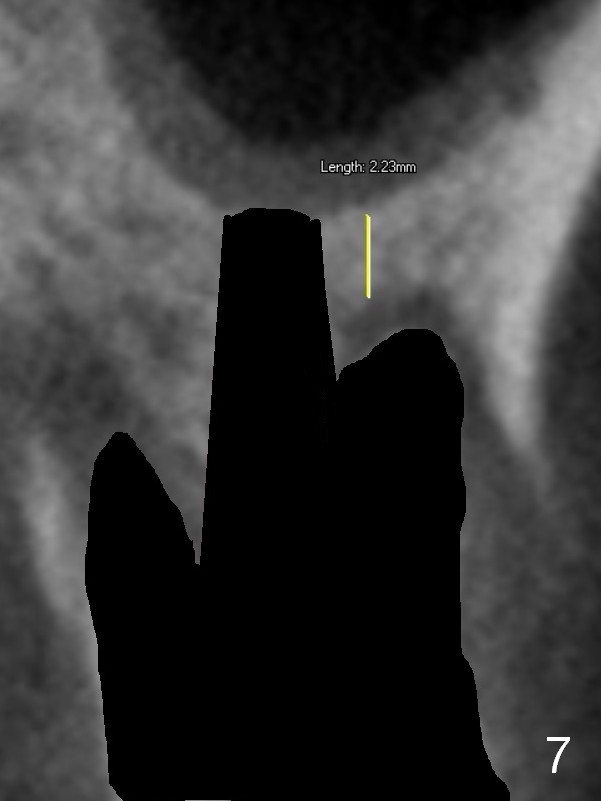

The septal bone is dense and the osteotomy is enlarged by alternating use of drills and expanders. By the time 3.8 mm ME is tapped in (Fig.6), the buccal plate of the septum is perforated. The ME is stable, in spite of the fact that it is only supported by 2-3 mm bone buccally (Fig.7). Continuously alternating use of MEs and drills leads to placement of a 5x11 mm implant with 30 Ncm insertion torque and sinus lift. After placement of bone graft (Fig.8 *) and 5x4(3) mm pair abutment (A), an immediate provisional is fabricated. Red dashed lines in Fig.6,9 represent the mesial outline of the socket, whereas black dashed in Fig.6 sinus floor. It suggests that the implant is stabilized by relatively small amount of native bone. Although IBS implants have aggressive thread patterns, a proper apical osteotomy should be prepared in the depth (perforates the sinus floor in this case) and diameter (4.3 mm drill) prior to placement.